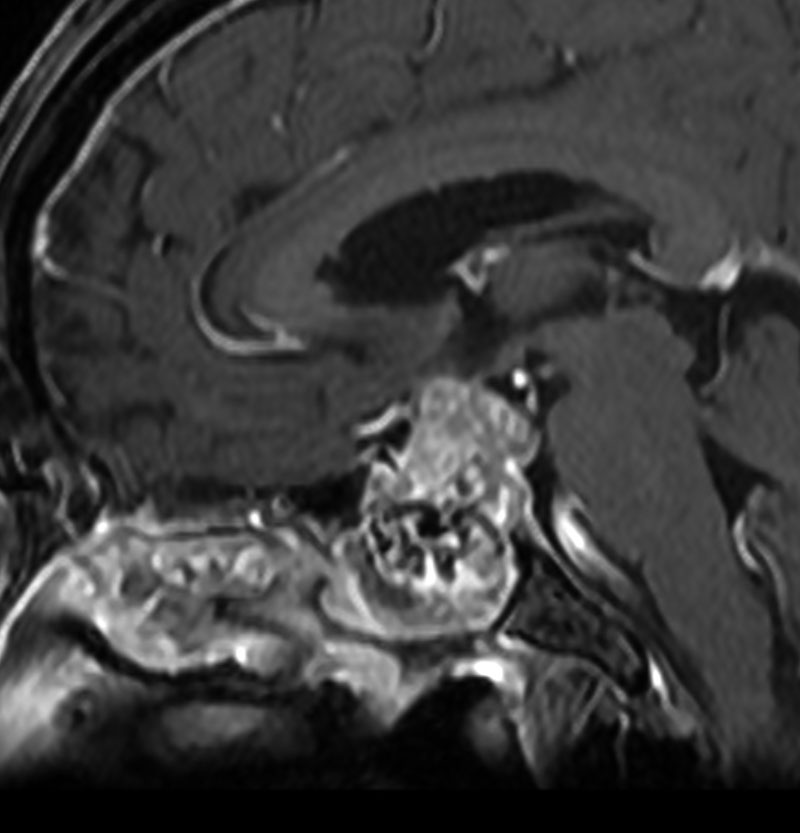

MRI T2強調画像(左)では等信号から高信号のまだらな境界が不明瞭な腫瘍が斜台から左海綿静脈洞内に浸潤しているのがみられます。T1強調ガドリニウム増強では,腫瘍がまだらに増強されています。トルコ鞍から鞍上部に伸び,視交差を侵し第3脳室底まで伸展しています。脊索腫が硬膜内に浸潤して神経組織と癒着することは珍しいことではありません。